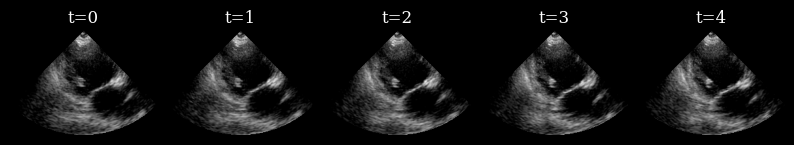

Visualize target sequence¶

Here we load a sequence of ultrasound frames from the CAMUS validation set. This will be our ‘ground truth’ target sequence, that the agent will need to reconstruct from a small budget of focused scan lines

n_frames_to_plot = 5

fig, _ = plot_image_grid(

data_sc[:n_frames_to_plot],

titles=[f"t={t}" for t in range(n_frames_to_plot)],

ncols=n_frames_to_plot,

remove_axis=True,

vmin=-1,

vmax=1,

)